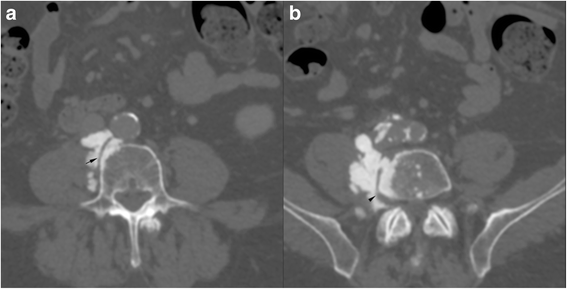

Case presentation: A 75 year-old patient was treated for a high grade transitional cell carcinoma of the bladder by surgery, chemotherapy and radiotherapy. Histology showed foci of bone metaplasia, both at the periphery of the tumor, and in a lymph node metastasis. 1 year later, a heterotopic bone formation was discovered in the right retroperitoneal space, near the lumbar spine, increasing rapidly in size during follow-up. Several imaging exams were performed (2 CT, 1 MRI, 1 Pet-CT), but in the absence of typical features of sarcoma, diagnosis remained unclear. Histology of a CT-guided percutaneous biopsy showed urothelial carcinoma and mature lamellar bone. Integration of these findings with the radiological description of extraosseous localization was consistent with a diagnosis of osseous metaplasia of an urothelial carcinoma metastasis. The absence of bone atypia in both the primary and metastases argues against sarcomatoid urothelial carcinoma with osteosarcomatous differentiation.

Conclusion: Osseous metaplasia of an urothelial carcinoma metastasis is unusual, and difficult to distinguish from radiotherapy induced sarcoma, or from sarcomatoid carcinoma. Rapid progression, sheathing of adjacent structures such as vessels (like inferior vena cava in our case) and nerves and bony feature of lymph node metastases necessitate histological confirmation and rapid treatment. Our case illustrates this disease and evaluates the imaging features. In addition we discuss the differential diagnosis of osseous retroperitoneal masses.